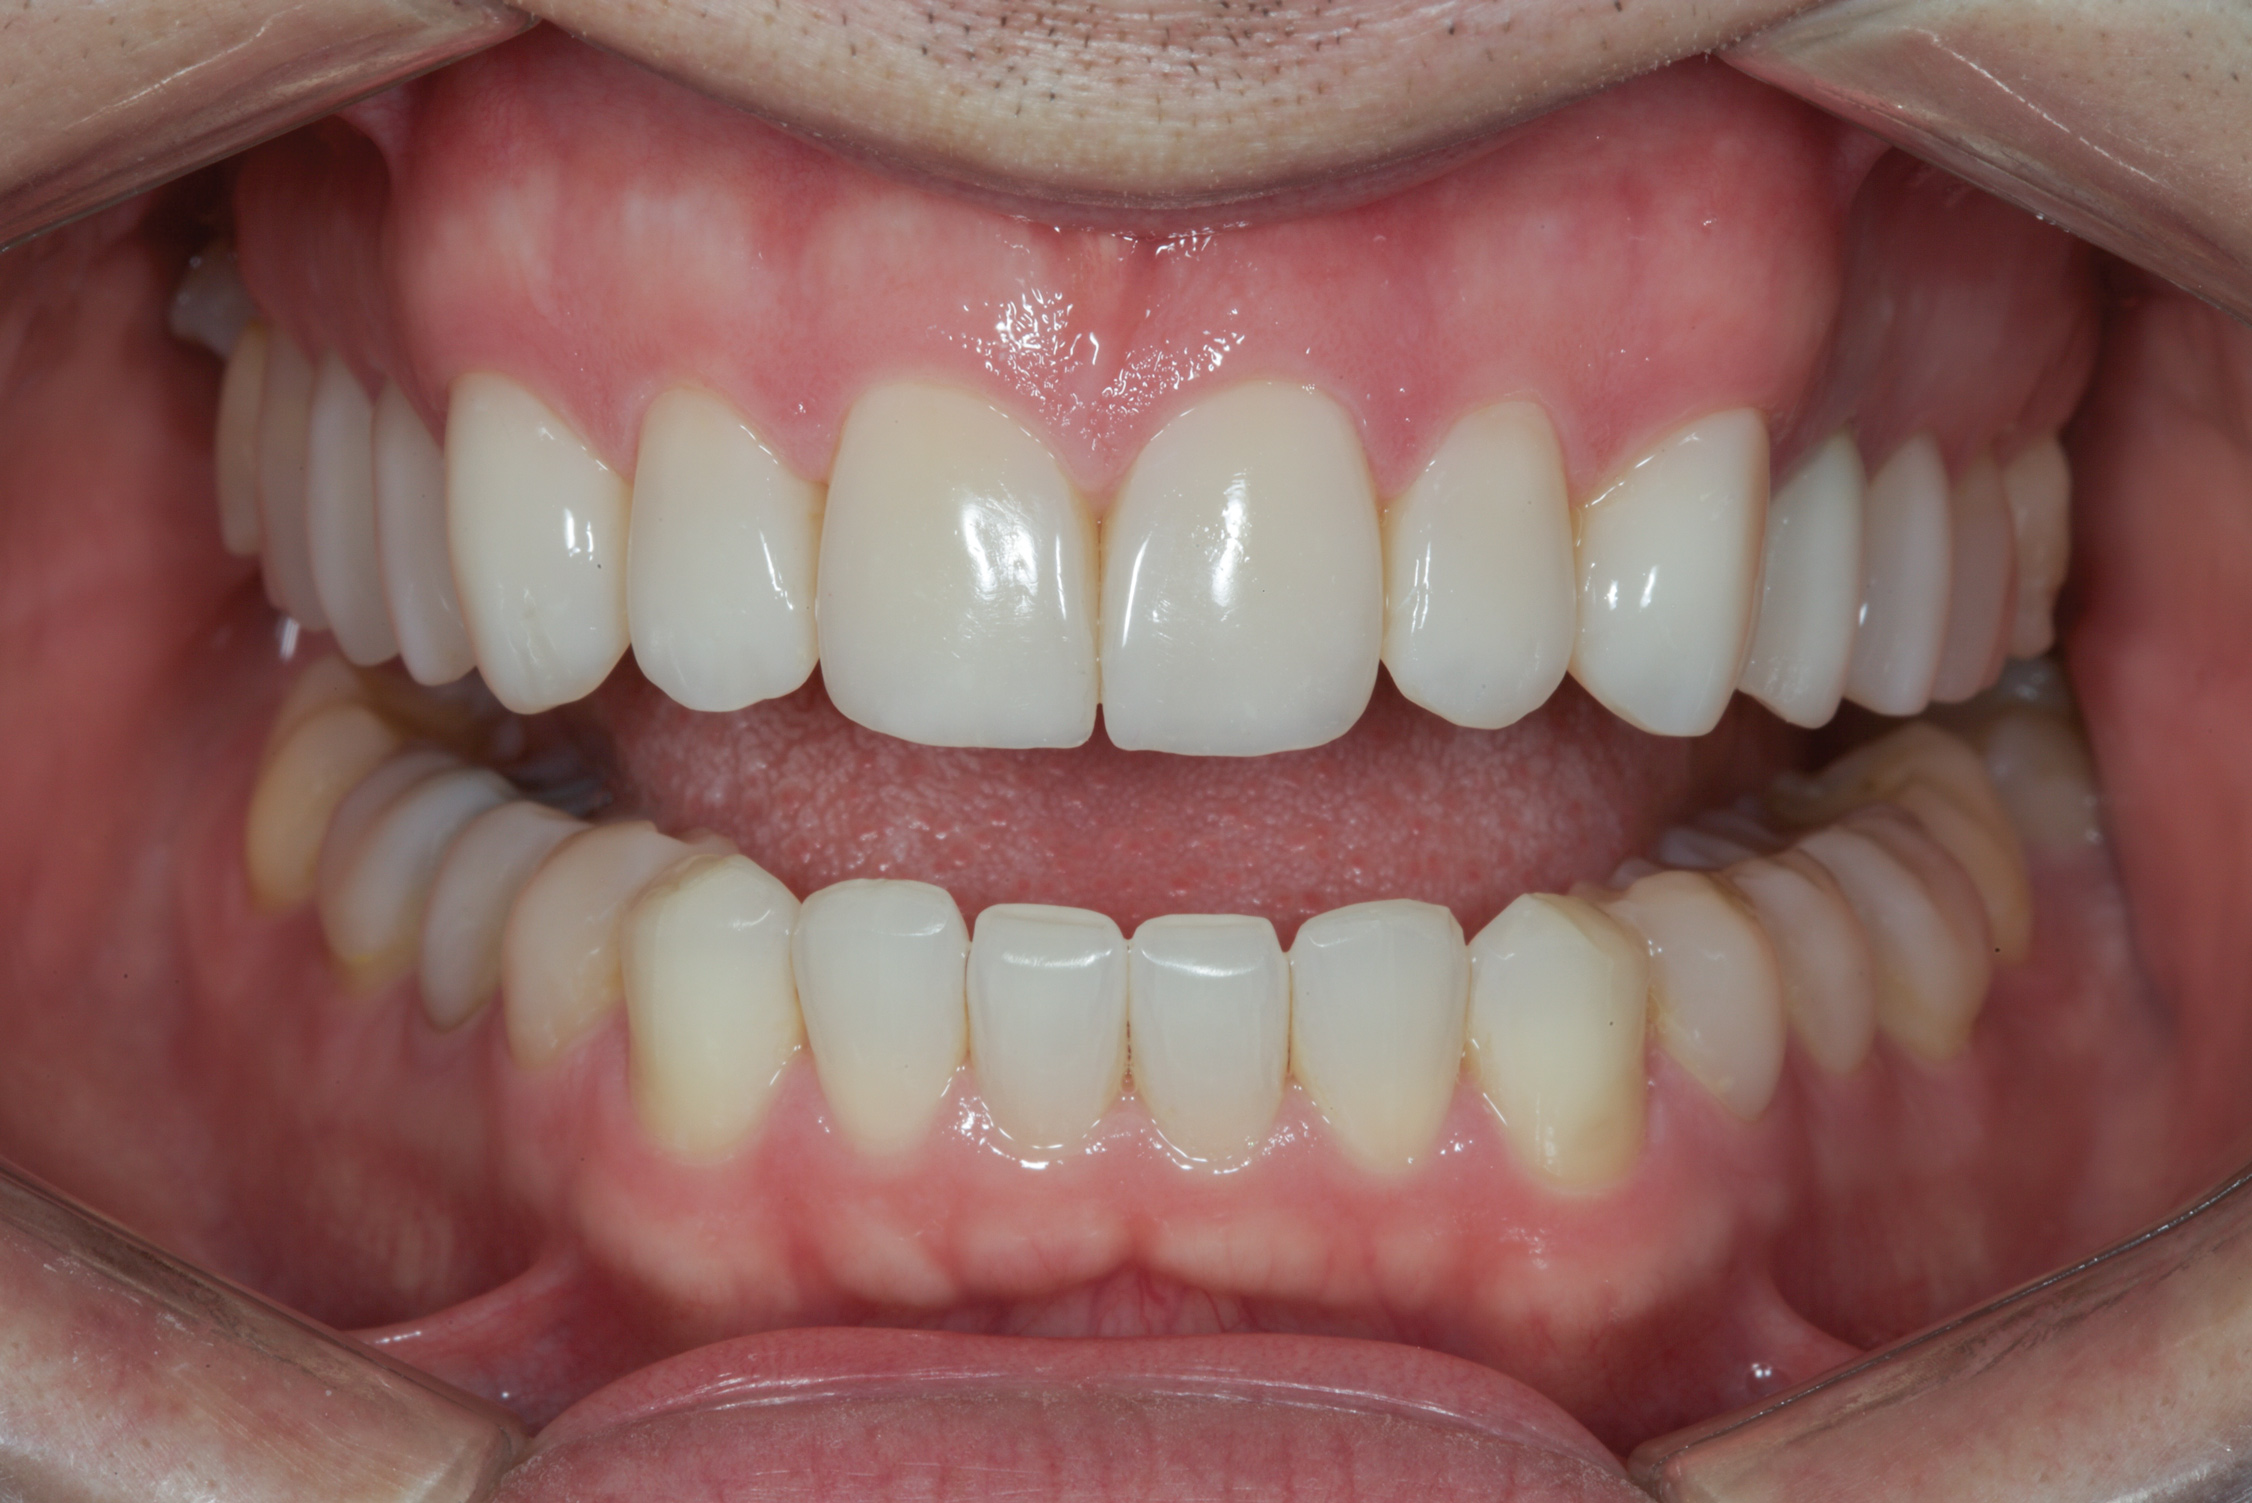

(11.) Postoperative retracted view.

Figure 11